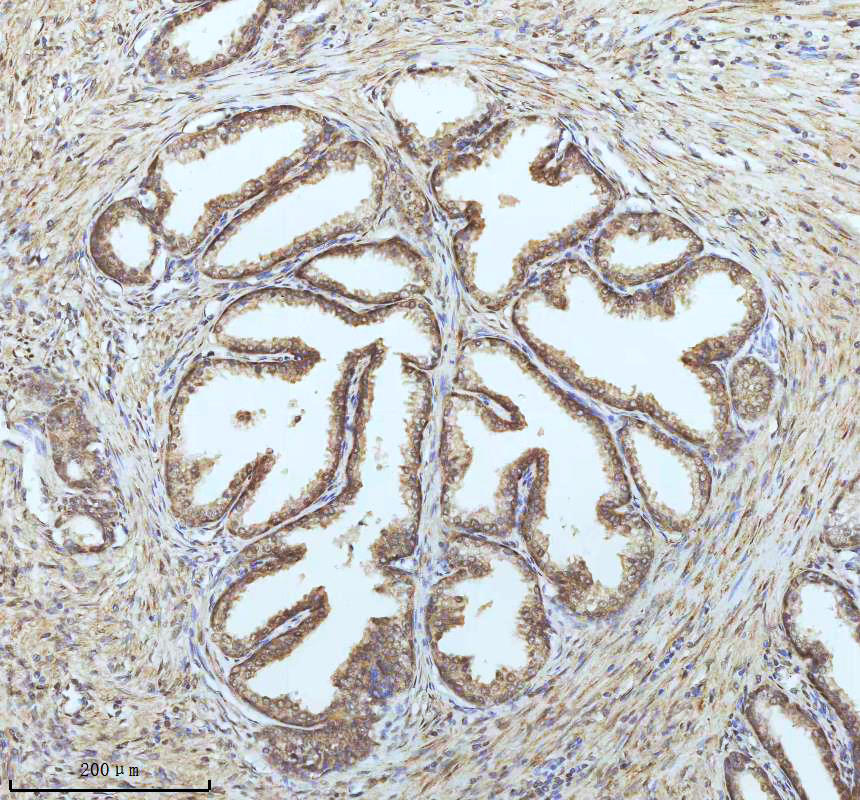

IHC analysis of PIN4 using anti-PIN4 antibody (M05181-1) .

PIN4 was detected in a paraffin-embedded section of human prostate cancer tissue. The tissue section was incubated with rabbit anti-PIN4 Antibody (M05181-1) at a dilution of 1:200 and developed using HRP Conjugated Rabbit IgG Super Vision Assay Kit (Catalog # SV0002) with DAB (Catalog # AR1027) as the chromogen.